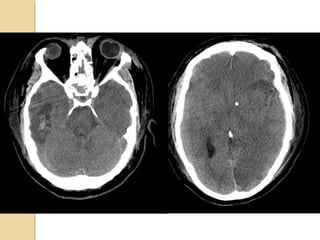

EPIDURAL HEMATOMAEPIDURAL HEMATOMA Locatedbetween the skull and periosteum Due to laceration of the middle meningeal artery or dural veins Can cross dural reflections but is limited by suture lines Lentiform shape (but concave shape in SDH)

SUBDURAL HEMATOMASUBDURAL HEMATOMA Occursbetween the dura and arachnoid Can cross the sutures but not the dural reflections Due to disruption of the bridging cortical veins Hypodense(hyperacute, chronic), isodense(subacute), hyperdense(acute)

• 12.